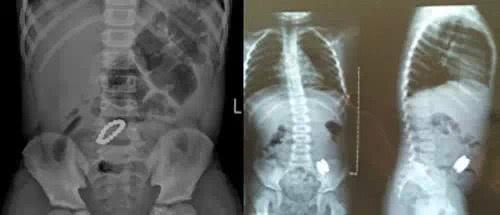

孩子被送到医院的时候手指已经黑了,左手冰冷,还伴随发烧症状。

医生表示,橡皮筋和人体组织类似,即便做核磁共振也不会被发现,一开始他们怀疑孩子是败血症,切开孩子手腕的红肿部位,才发现是橡皮筋“跑”进了手腕里。

浙江省也有一名2岁女童把橡皮筋绑在手上,等到家人发现的时候,手臂已经红肿,出现一道深深的勒痕。